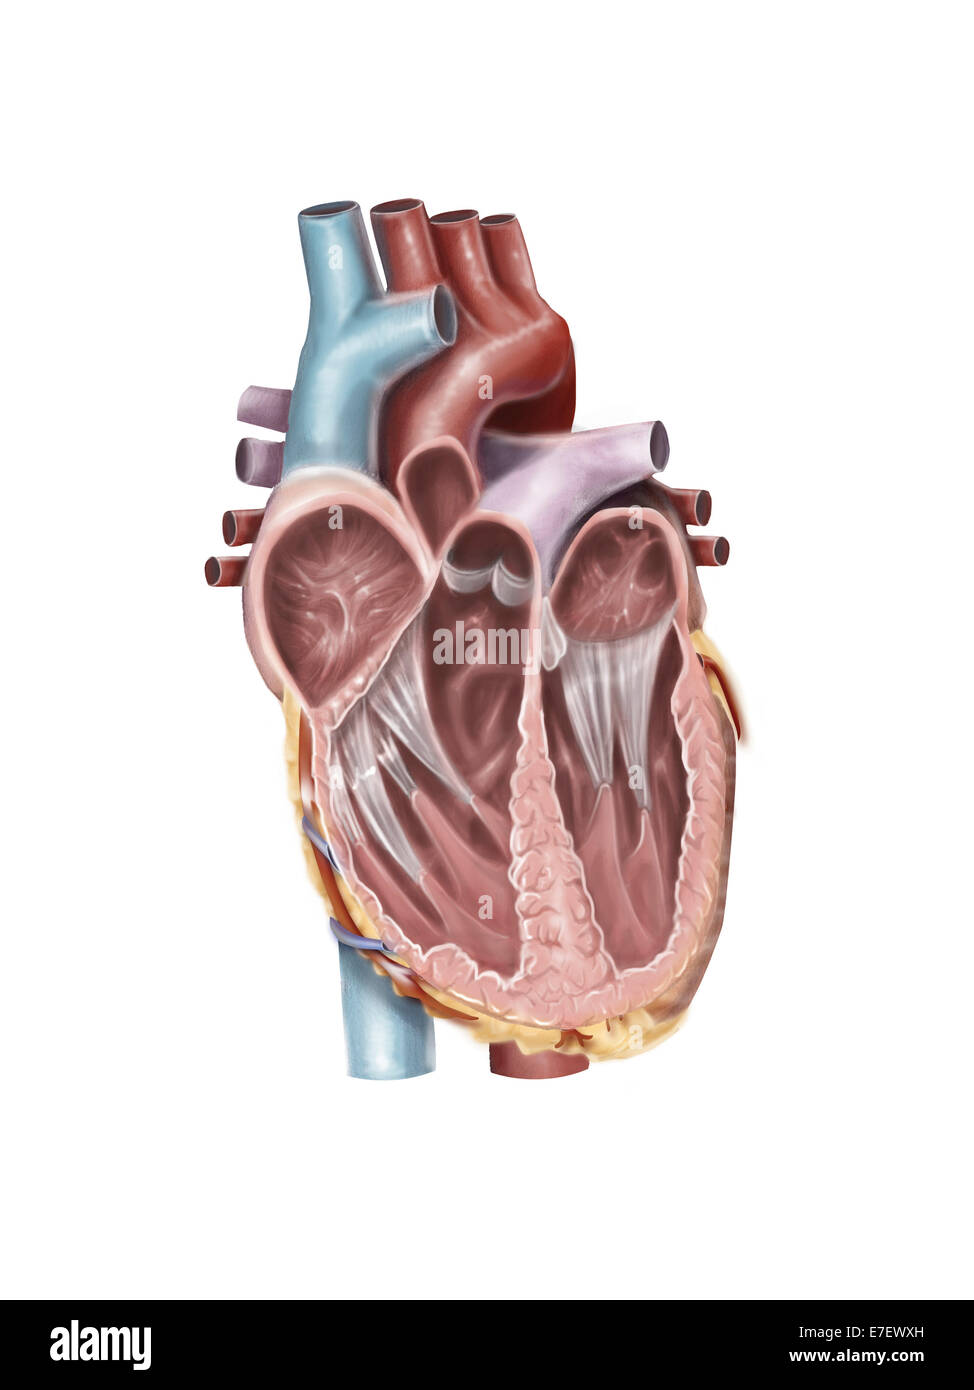

Internal view of the human heart. Stock Photohttps://www.alamy.com/image-license-details/?v=1https://www.alamy.com/stock-photo-internal-view-of-the-human-heart-73471736.html

Internal view of the human heart. Stock Photohttps://www.alamy.com/image-license-details/?v=1https://www.alamy.com/stock-photo-internal-view-of-the-human-heart-73471736.htmlRFE7EWXG–Internal view of the human heart.